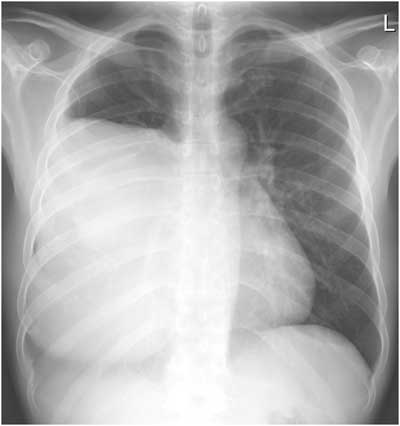

There is no air-fluid level seen on either view to support the diagnosis of pleural effusion, and the lateral view clearly demonstrates a mass-like lesion, the epicenter of which lies in the anterior mediastinum. Developing a differential for a mediastinal mass requires understanding its boundaries and divisions. The boundaries of the mediastinum itself are the thoracic inlet, the diaphragm, and the pleural sacs. The anterior division of the mediastinum extends from the sternum to the pericardium and brachiocephalic vessels, the posterior division extends from the pericardium and trachea to the vertebral column, and the middle division fills the space between the anterior and posterior mediastinum (Table 1)(5). This patient presented with an anterior mediastinal mass, the most common of which are thymomas, teratomas, thyroid malignancies, and lymphomas. Of these, thymoma has the highest incidence, representing 50% of all anterior mediastinal neoplasms in adults. Thymomas most often develop between the ages of 40-60 and only a third of patients will develop symptoms directly related to the tumor’s effects on surrounding structures. As a result, the diagnosis is often made as an incidental finding on a chest radiograph obtained for other causes. Most thymomas are indolent tumors, which may appear solid, cystic, or hemorrhagic on computed tomography, and up to 50% of thymomas will demonstrate some sort of paraneoplastic syndrome. Distant metastases are uncommon (<7%); however, local invasion can occur up to 32% of the time (5-8).